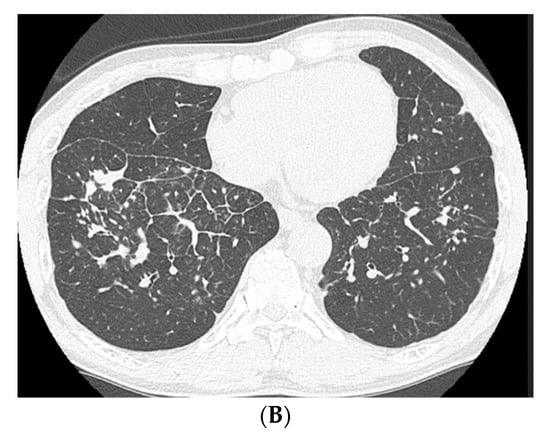

2. Case Presentation